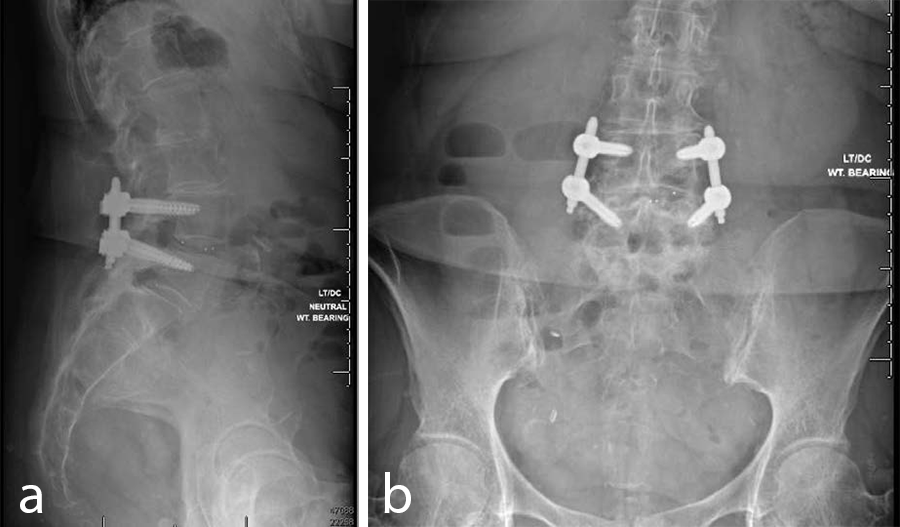

- VIPER PRIME™ Screws and CONCORDE™ Bullet Interbody Cage (Fig 10)

Outcomes

- The patient did well and stayed one night at the hospital.

- At the 6-week postoperative follow-up she was pain free.